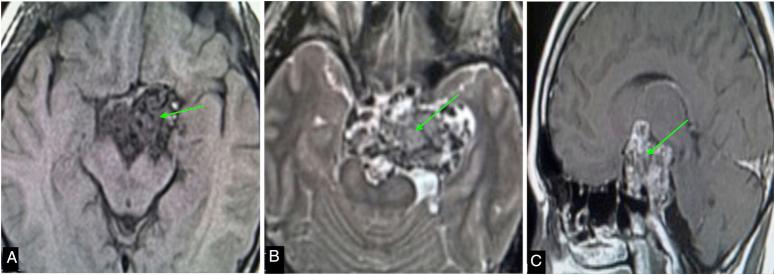

A 34-year-old man with vision deterioration and headaches had an MRI revealing a suprasellar lesion. Intraoperatively, a bony hard tumour was partially resected. Subsequent computed tomography (CT) confirmed a calcified mass contiguous with the posterior clinoid.

一名34岁视力减退且头痛的男性,MRI显示鞍上病变。术中部分切除了一个骨质坚硬的肿瘤。随后的计算机断层扫描(CT)证实有一个与后床突相连的钙化肿块。